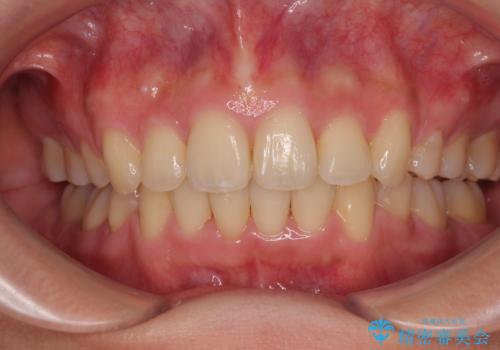

全顎的なデコボコと口元の突出感 ワイヤー装置での抜歯矯正で整った口元に